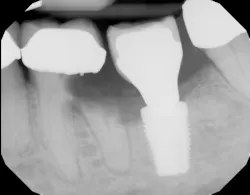

- Thinning of the hard and soft tissues around the dental implant (figure 2), which can increase the risk of a failed implant if tissue support is compromised

- Changes in occlusal patterns and force distribution, leading to possible fracturing of the implant components (figure 2a). Such changes can increase the risk of a failed implant and may require additional implant treatment to restore function and stability.

Gum recession around dental implants due to craniofacial development is a significant concern in implant dentistry, with the potential to undermine both the esthetic and functional success of dental implant procedures. When the gum tissue surrounding the implant site begins to recede, it can expose the underlying adjacent tooth root or the surface of the dental implant itself (figure 5). This not only affects the natural appearance of the artificial tooth but also increases the risk of dental implant failure and other complications.

For patients who already exhibit signs of gum recession around their dental implants, advanced treatments such as bone grafting may be necessary to restore the supporting bone and stabilize the implant (figure 6). Addressing the underlying causes—such as correcting poor oral hygiene habits, managing teeth grinding, and treating existing gum disease—is critical to prevent recurrence and ensure the longevity of the implant.